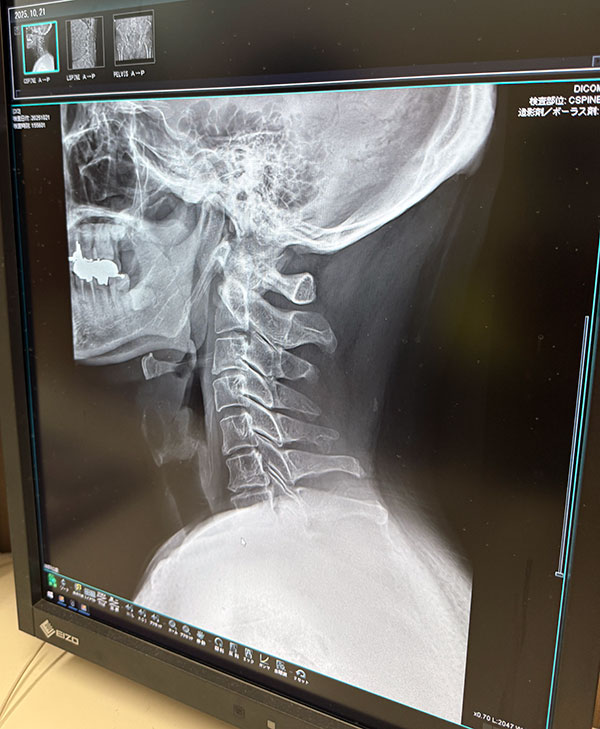

| 2025/10/21火 楓の森で検査 ↓前 次↑ 朝イチ女王送ってクルっとひさ枝へ。 ![]() 8:30ぐらいですが少し落ち着いてきたのかな。 ![]() 姉やんから頼まれたお土産うどん買いがてらでしたが久々釜玉かけを。うむ、自分にとってのこの店はやっぱこれやな。 ![]() 主治医モリケン先生のトコにも行きます。受付の美女に「いつもの膝ですか?」→「はい、それに加え腰と尻と首と。。」→「事故か何かで?」→「いや転んだと言うか。。」→「いつですか?→「10/18土です」てか 「先生も知ってますので」 ※その場にいたw というやりとりをしました!レントゲン撮ってもらいました。 ![]() ドキドキしながら結果を。 ![]() 首は一箇所狭まってるそうで、今回のが原因ではなく加齢とのこと。ヨシキよりかはマシでしょう。 ![]() ヒビ等はないようです。 ![]() 椎間板はもうすぐヘルニアかもやけど、それは元々やからなあ。 ![]() パイプ椅子で頭打ったけどそれなかったらもっとヤバかったかもとのことでした、ともかくHOTしつつ 正式に椅子アクションを禁止 ※ジャンプもデス されました。新しい面白いコトを探しましょう。 ![]() いつもの膝ヒアルロン酸デュアル打ってもらって後に。 ![]() ひさ枝でもらった麺で寄せ鍋ですか。 ![]() 土曜のライブや日曜からの九州出張までに痛さマシになってて欲しい。 ↓前 次↑ | ||